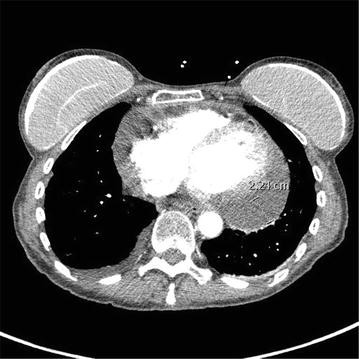

Fig. 1From: Conservative management of nivolumab-induced pericardial effusion: a case report and review of literatureCT angiography of the chest demonstrated a large pericardial effusion of 2.4 cm thickness after treatment with first dose of nivolumabBack to article page